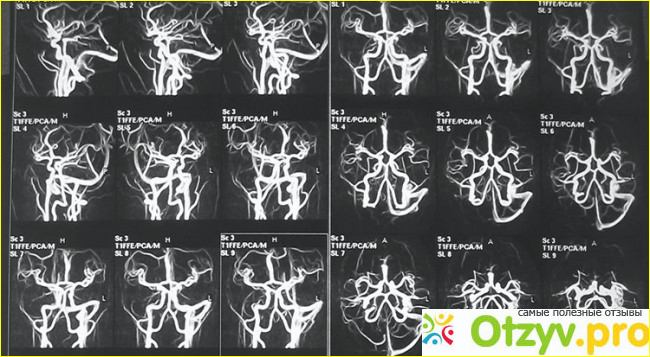

Основное, что надо знать - это то, что МРТ сосудов головного мозга бывает двух видов - это бесконтрастное и контрастное. Именно бесконтрастный метод, в виду своей безопасности и самый распространенный и самый часто назначаемый себе без врача. Почему безопасный? Да потому, что при введение контрастного вещества в вену могут наблюдаться аллергические реакции, вплоть до анафилактического шока, так что судите сами. Но иногда он необходим, когда бесконтрастное обследование не видит патологии сосудов. Итак, что показывает МРТ сосудов головного мозга. Просто анатомию сосудов. Некоторые больны спрашивают со страхом о том, что у них там какой-то Виллизиев круг нашелся. Ну так, это просто так сосудистые анастомозы в головном мозге называются - это большие артерии объединяются между собой посредством более мелких. Например передние мозговые артерии соединяются поперечным анастомозом - передней соединительной артерией.

Но бывает такое, что некоторые анастомозы у человека отсутствуют, и например, при инсульте, когда закупоривается сосуд справа, то кровь из левого полушария не может попасть в правое из-за отсутствие этого самого анастомоза. То есть Виллизиев круг может быть вовсе не кругом, то есть не быть замкнутым, и у человека при инсульте могут возникнуть гораздо большие проблемы, чем у человека с полным нормальным кругом. Но это так, для прогнозов, а ведь инсульт совершенно необязательно должен случиться у человека. А МРТ сосудов головного мозга необходим для выявления сосудистых аномалий. Опасных для жизни. Например аневризм и артерио-венозной мальформаций. Но эти аневризмы и мальформации, если они большие можно увидеть и на обычном МРТ головного мозга. А если маленькие, то их иногда не видно и на МРТ сосудов. Например случилось у молодого человека кровоизлияние в мозг, то есть наверняка была врожденная аневризма (хотя бывают и приобретенные на фоне артериальной гипертонии, например) и надо ее оперировать, но прежде желательно увидеть на МРТ, чтобы знать куда лезть.